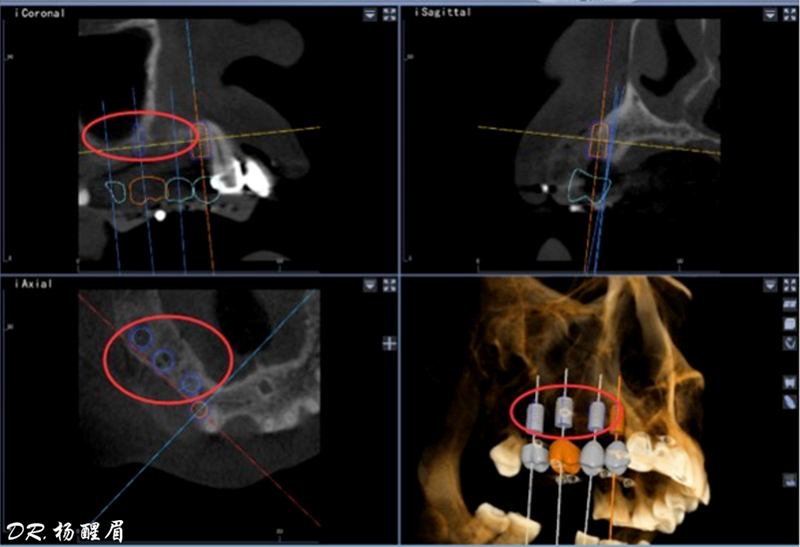

®石膏模型上進行排牙確定患者咬合關系,取放射阻射材料灌于缺牙區(qū),患者戴著處理過的

配準裝置拍攝術前CBCT。

®根據(jù)CBCT中牙冠顯影位置,按照修復引導種植的原則進行方案設計

®使用迪凱爾易植美導航軟件進行方案設計,確定種植體使用方案,以及種植位點,方向和深度

®多顆植體種植方案應盡量保持軸向在同水平線上

®該患者需連續(xù)種植三顆植體,手術難度高。需保證相鄰植體位置關系符合種植要求。徒手種植難以保證其位置一致性。

®主刀醫(yī)生經(jīng)驗豐富,通過石膏模型排牙確定咬合關系,放射阻射材料提前放入缺牙區(qū),確定CBCT中牙冠位置,擺放種植體。遵循修復引導種植原則。

®如果翻瓣后發(fā)現(xiàn)患者實際情況與種植設計不符,迪凱爾易植美軟件能及時調(diào)整手術方案。主刀醫(yī)生使用導航軟件無需借助額外輔助工具,對種植過程中術區(qū)散熱以及開口度和視野都無影響。